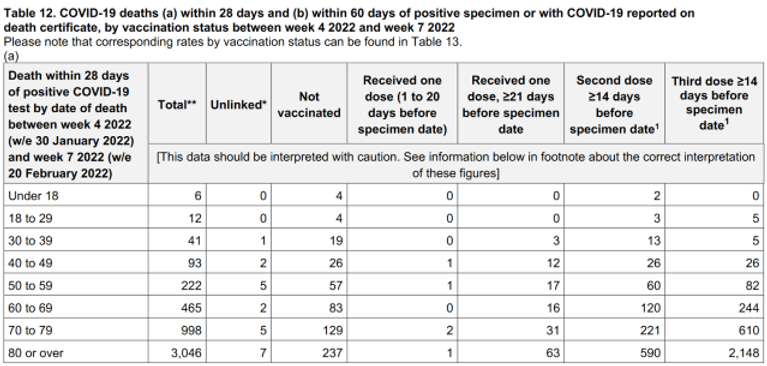

Table 12, found on page 43 of the latest report shows the number of Covid-19 deaths by vaccination status in England between the 24th of January and the 20th of February, 2022, and it confirms yet again that the vast majority were recorded among the triple vaccinated population.

Source –

In all, there were 4,861 Covid-19 deaths between 24th of January and the 20th of February, 2022, and the triple vaccinated population accounted for 3,120 deaths. Whilst the nonvaccinated population accounted for just 559 deaths.

Overall, the vaccinated population accounted for 89% of all Covid-19 deaths during these four weeks, with 4,302 recorded deaths. This means the vaccinated population now account for 9 in every 10 deaths, and the triple vaccinated population account for 4 in every 5 deaths.